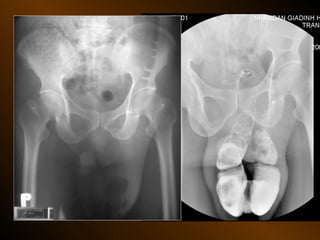

TỤ DỊCH TRONG PHÚC MẠC

• X QUANG QUY ƯỚC

– Trong tiểu khung

– Dọc hai bên hông

– Giữa bụng

• SIÊU ÂM

– Phản âm trống, chuyển dịch

– Lượng ít

– Bản chất dịch

• X QUANG CẮT LỚP ĐIỆN TOÁN

– Mật độ

– Vị trí

– Nguyên nhân

TỤ DỊCH KHU TRÚ

– Tụ dịch ? – khối u ?

– Phản âm, chất chứa, vỏ bọc ?

– Mật độ, bắt cản quang ?